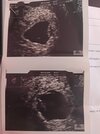

A masz może zdjęcie?No właśnie znowu nie i nie kazał na niego patrzeć omija jego temata w porównaniu do zarodka to jakieś 7mm ma, co mnie cały czas martwi.

Nie widać go dobrze, ale jest cały czas sporyA masz może zdjęcie?